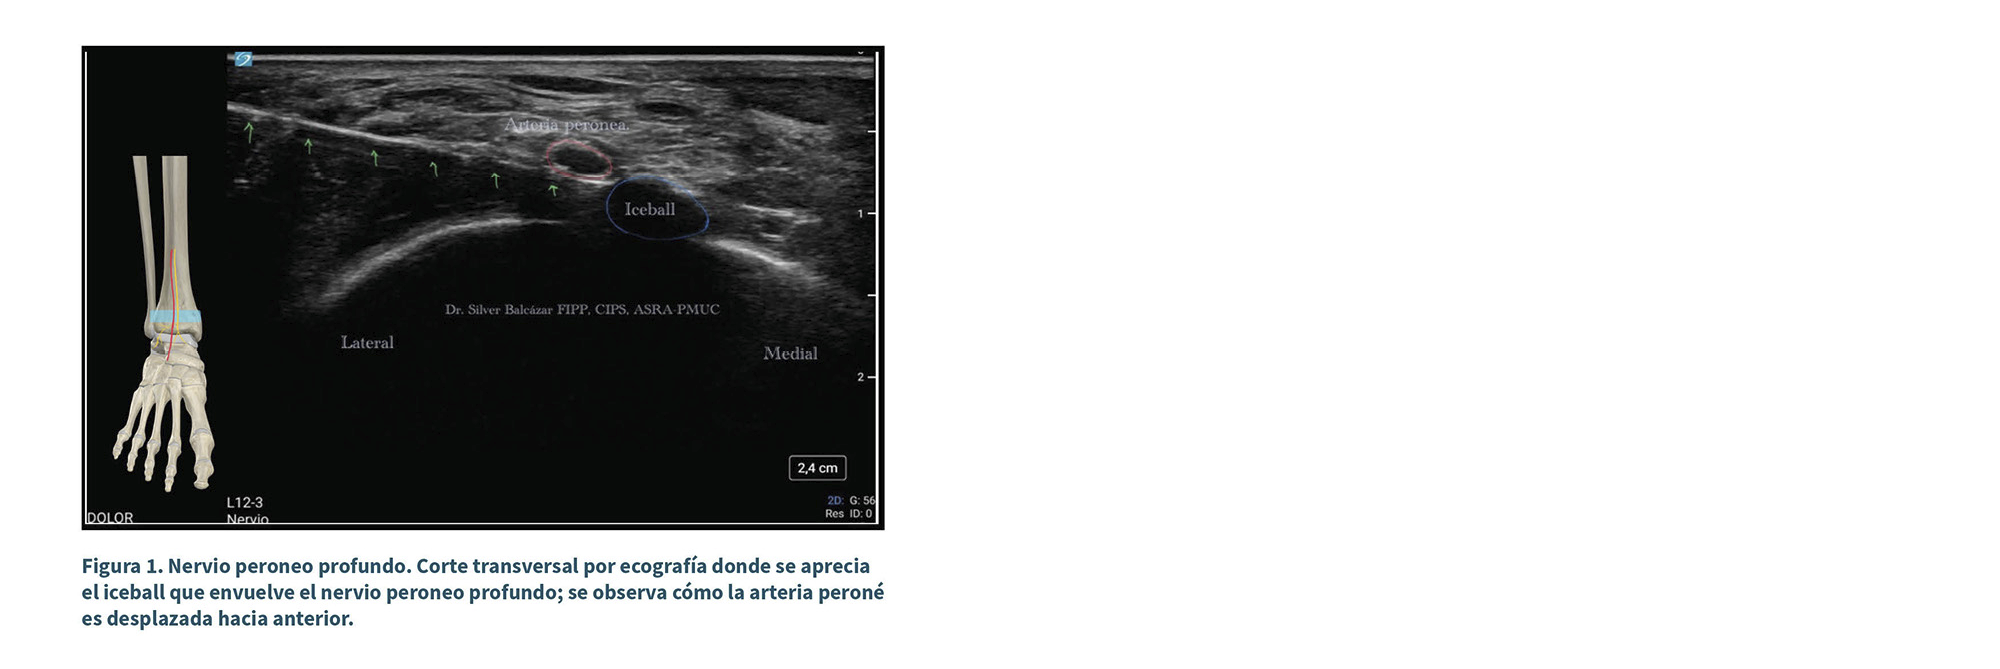

Nervio peroneo profundo: con transductor lineal 12 MHz en posición transversa entre la línea intermaleolar se identifica arteria peronea, medial a esta, el nervio peroneo profundo. Previa infiltración de la piel con lidocaína al 1 % se puncionó de lateral a medial, inferior a la arteria, con introductor de 14 G, y a través de este, la sonda de crioneurólisis. Se obtuvo estímulo motor, sin respuesta, por lo que se realizaron 2 ciclos de ablación de 2 minutos, -88 °C, con tiempo de defrost de 30 segundos entre cada ciclo (Figuras 1 y 2).